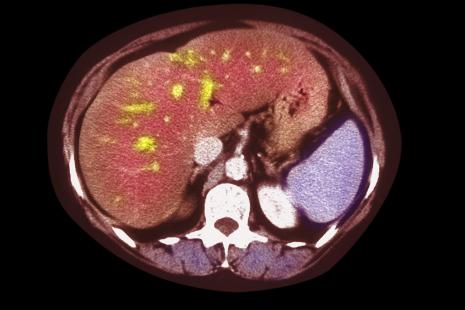

La stéatose hépatique non alcoolique (NAFLD), caractérisée par une accumulation de graisses dans le foie, est l’une des maladies hépatiques chroniques les plus fréquentes avec une prévalence de 20 à 30 % en Europe. Elle se répand dans le monde entier, en corrélation avec l’épidémie d’obésité et de syndrome métabolique. Elle peut débuter dans l’enfance, majorant les risques de diabète de type 2 et de maladie cardiovasculaire.

Une forme plus sévère de NAFLD, la stéatohépatite non alcoolique (NASH), associant stéatose, inflammation hépatique et lésions des hépatocytes (avec ou sans fibrose), majore le risque de progression vers la cirrhose et le carcinome hépato-cellulaire. Sa prévalence serait de 2 à 5 % aux États-Unis.